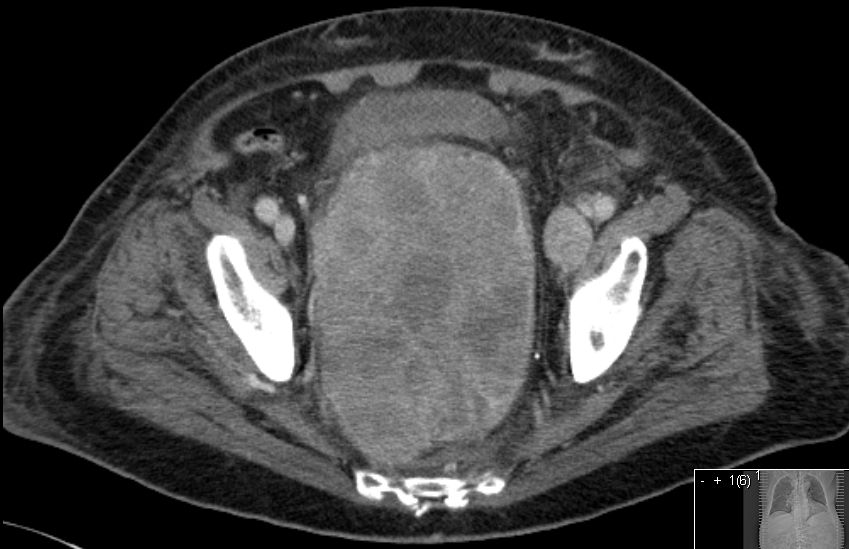

81-jähriger Mann mit einem Prostatakarzinom

seit 2 Jahren. Der Tumor füllt das kleine Becken aus. Urinableitung durch

DK. Rektale Blutung, kein Ileus! PSA 198.500.![]() | ||